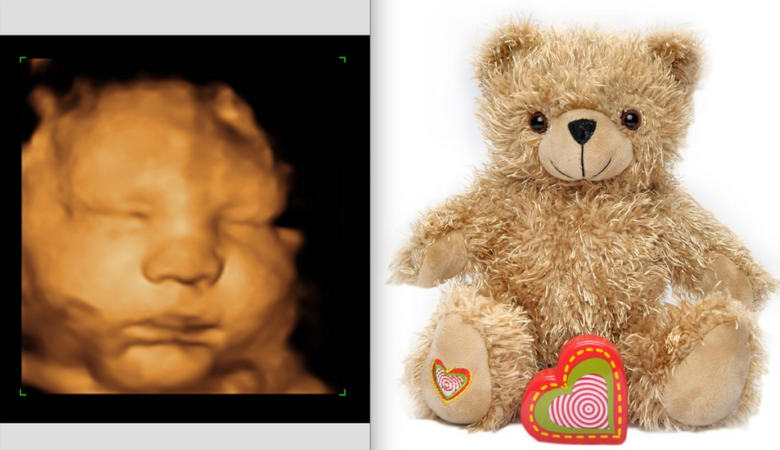

A 3D sonogram is a beautiful and memorable experience for expecting families. Unlike regular ultrasound, a 3D sonogram shows a clear view of the baby’s face and body. Many parents love it because they can see their baby in more detail. During a 3D sonogram session, a professional technician will perform the scan in a […]